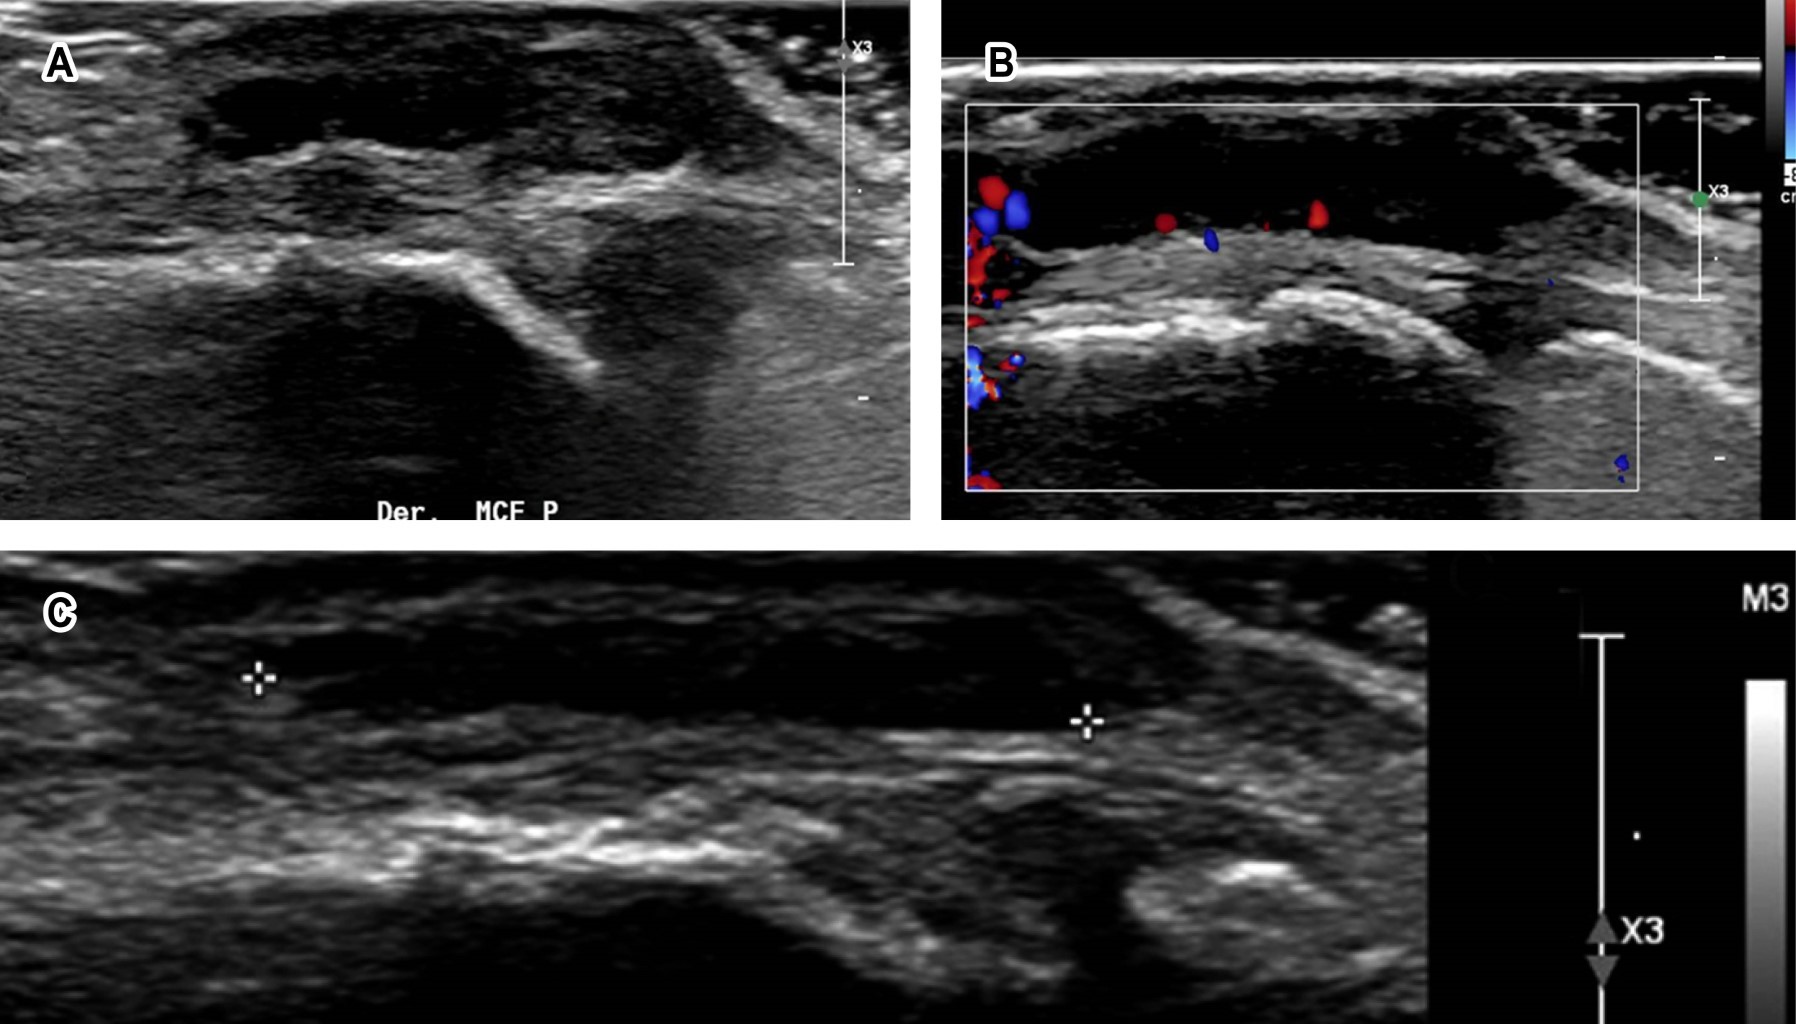

Giant cell tumors of the tendon sheath, corresponding to 50% of hand tumors, are nodular lesions between 30-50 years of age, predominating in females, usually on the volar or lateral surface of the fingers, close to the DIP joint. Suspicion diagnosis is clinically supported by ultrasound, which identifies a solid lesion, homogeneous, hyper, or hypoechoic, occasionally heterogeneous, about the tendon sheath. With vascularization on Doppler, it can be confused with synovial cysts; MRI is the choice for diagnosis. Treatment is the complete removal of the lesion. Radiotherapy, although controversial, could be indicated in cases with recurrence risk.

Figure 1

Figure 2

Figure 3